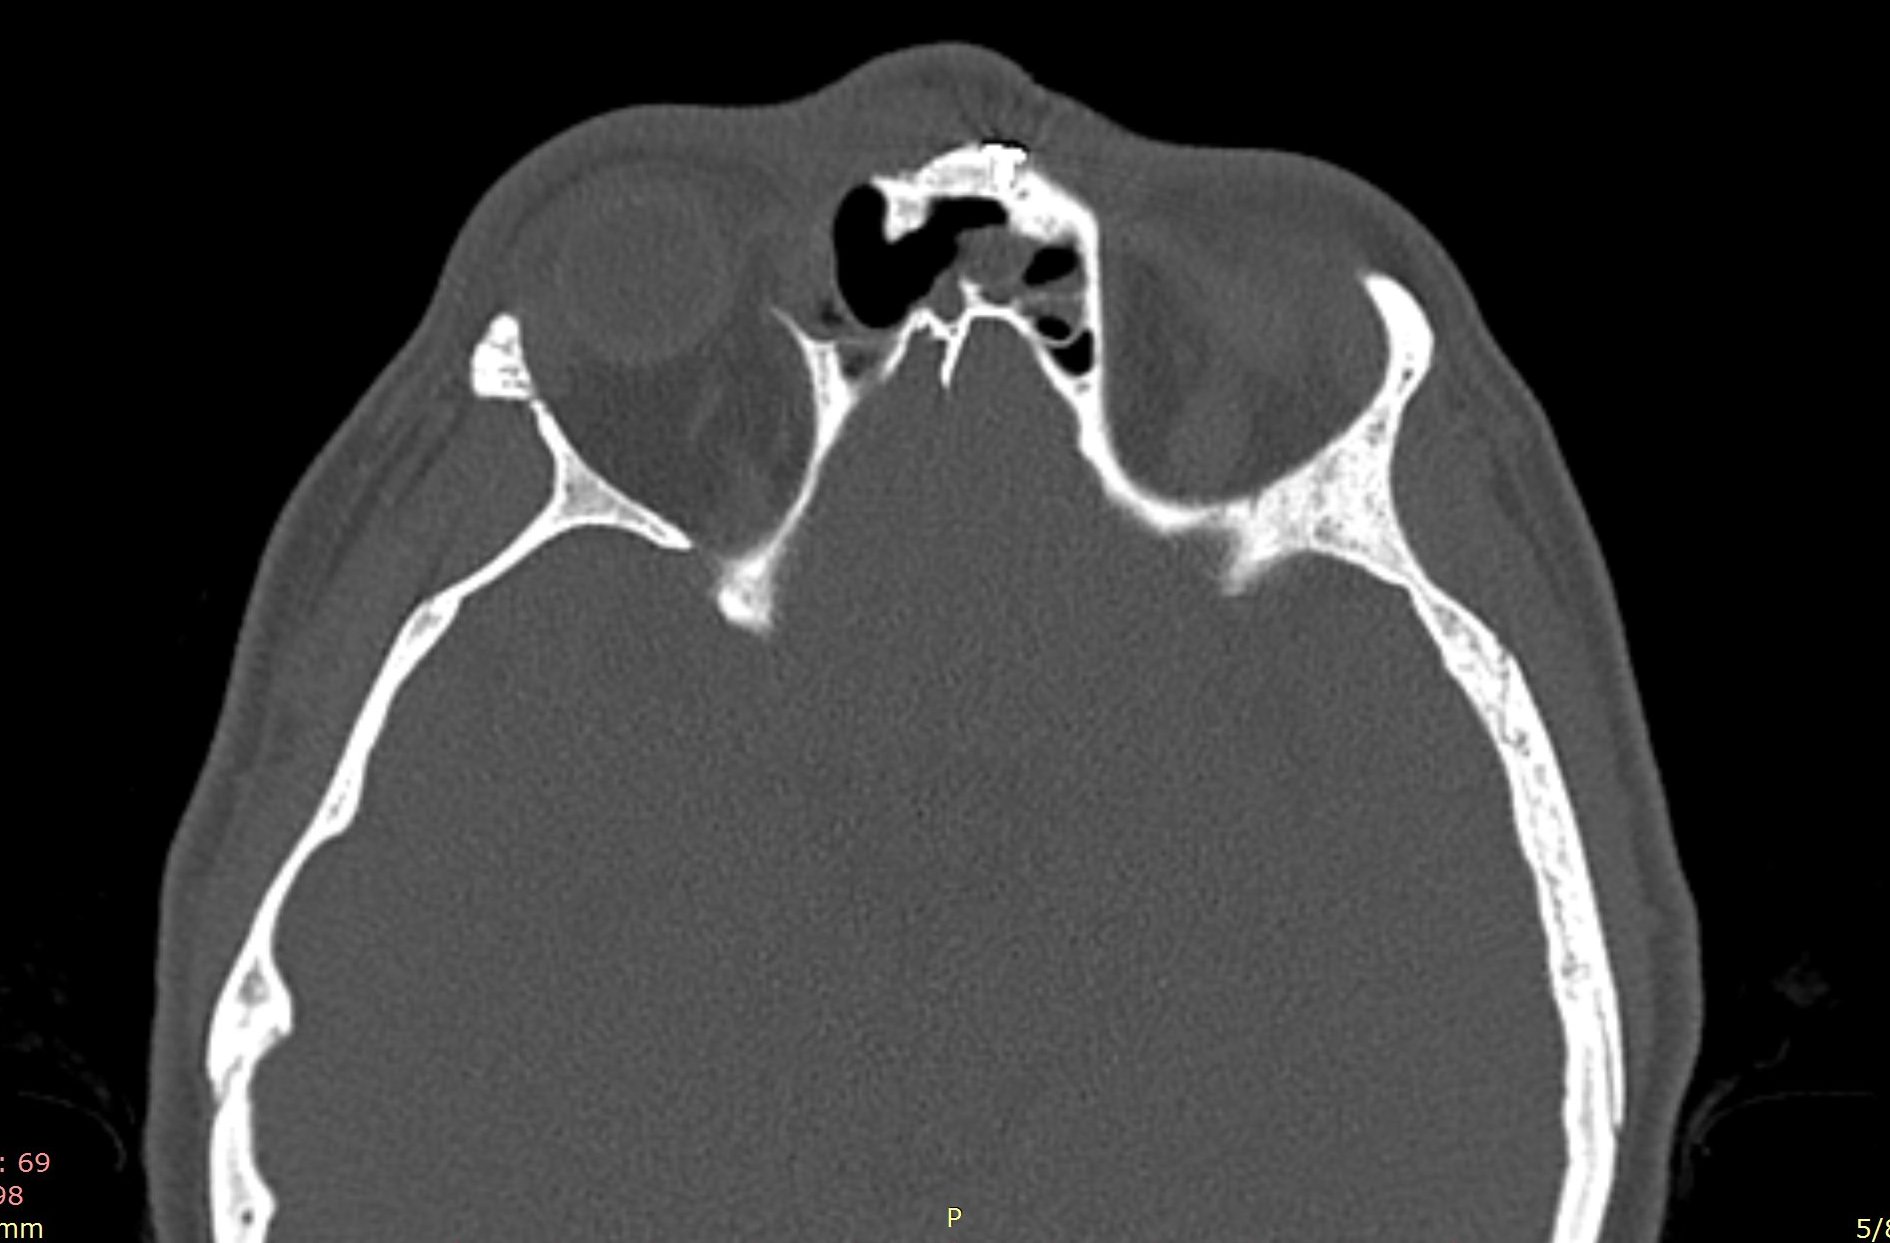

Ziua 1 postoperator, pacienta efectuează CT sinusuri paranazale de control care certifică ablația completă a formațiunii.